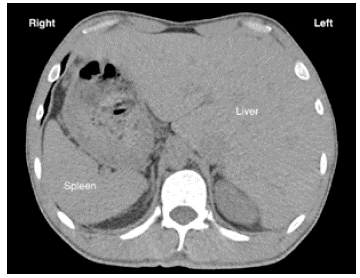

After finding dextrocardia, it was necessary to ascertain visceral situs (normal, inverted, ambiguous). A simple tomography documented pulmonary bronchiectasis, as well as liver on the left side (Figure 4), leading to suspect KS; this was confirmed with findings of chronic sinusitis in paranasal sinus tomography. In addition, HRCT showed tomographic signs of infectious bronchiolitis.

The positions of the organs are known as situs solitus (left heart, right liver), situs inversus (right heart, left liver) or situs ambiguus (some organs in an abnormal position, with others in normal position). Alterations in the genes that cause PKD lead to random situs (half of the individuals with situs inversus and the other half with situs solitus). 4

Situs inversus abnormalities can be recognized by conventional radiography and ultrasound. CT provides good anatomical detail of the specific condition, while MRI can be useful to assess patients with cardiac abnormalities. 6,17